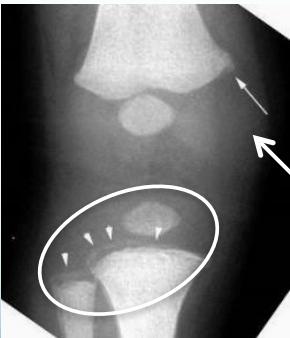

Beware! Malignant Tumors

- Can present as injury

- History of trauma is usual

Case Example:

- 12-year-old girl

- History of trauma

- Mild tenderness

- Periosteal reaction

- Initially diagnosed as injury

- 2 months later, still tender

- Final diagnosis: Ewing’s sarcoma